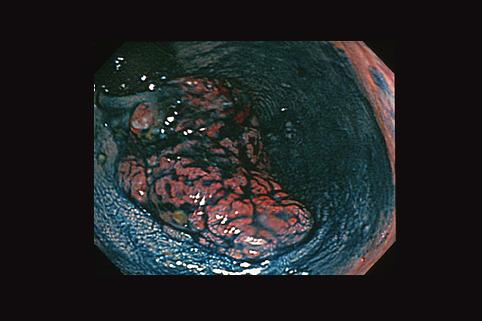

질환(병리주체)의 분류 악성 상피성종양/미분화암

부위(장기별) 대장/직장

검사방법 내시경

종양의 육안분류 1형(종괴형)/

종양의 최대경(밀리미터) 40이상

종양의 심달도 mp